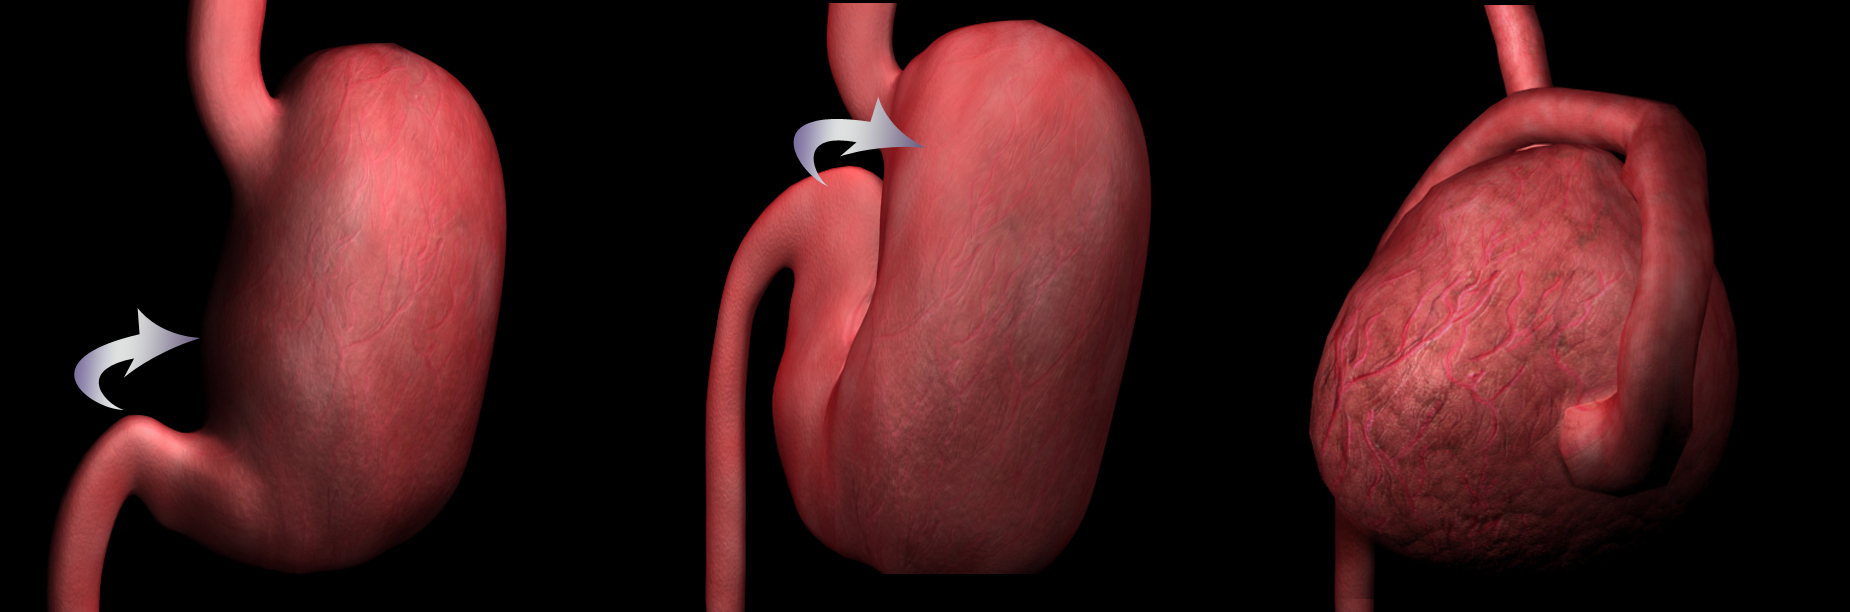

A következő ábrán jól látszik a csavarodás anatómiája:

Kép: http://petpagesatlanta.com/